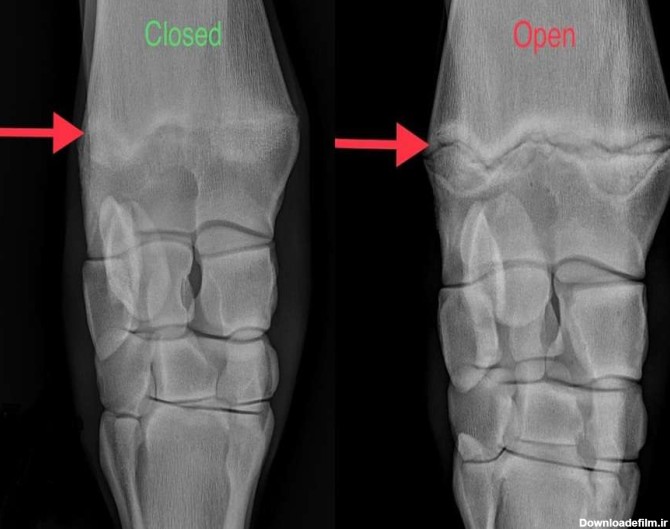

اندازه گیری سن استخوانی در حوزه پزشکی کودکان، از اهمیت بالایی برخوردار است و به بررسی رشد اسکلتی می پردازد و ممکن است با سن شناسنامه ای کودک هماهنگ نباشد. با ما همراه

سن استخوانی در علم پزشکی از اهمیت بالایی برخوردار است و در حقیقت رشد اسکلتی را بررسی و ارزیابی می کند که امکان دارد بیشتر یا کمتر از سن شناسنامه افراد باشد. این دو یکی نیست.